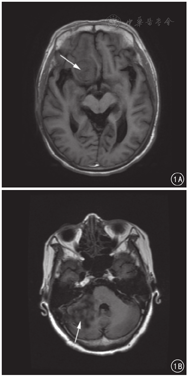

低级别组脑膜瘤大多形态规则,呈团块状或结节状,部分可呈边界清楚的浅分叶状;高级别组脑膜瘤形态多呈不规则,边缘不清楚。低、高级别组脑膜瘤的肿瘤边缘不规整、强化不均匀、边缘水肿区、脑膜尾征和囊变、坏死、钙化区的发生率差异均有统计学差异(P值均<0.05)。见图1、表2。

52例低级别组脑膜瘤中有38例DWI、ADC均呈等信号,14例DWI呈稍高信号、ADC呈稍低信号;16例高级别组脑膜瘤实质部分DWI均呈高信号、ADC均呈低信号,而囊变、出血坏死、钙化区均呈高信号。见图2,图3,图4。